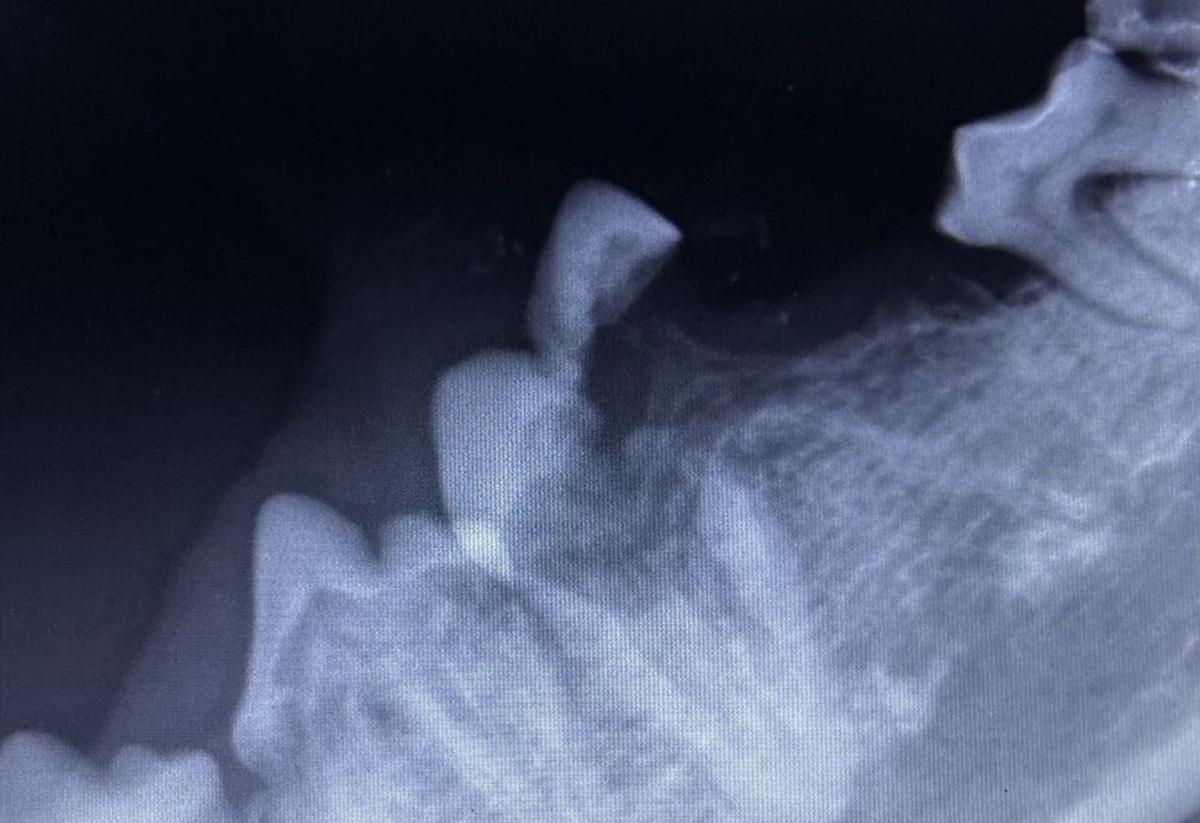

Imagen radiológica de la dentadura de un perro. | / FOTOS: CENTRO VETERINARIO PITIUSO

Las radiografías dentales permiten diagnosticar enfermedades que no son visibles con exploraciones rutinarias. Por ello es interesante realizarlas con el fin de detectar dolencias que afectan a la calidad de vida de perros y gatos

En las exploraciones orales rutinarias, el veterinario solo puede ver la parte externa de los dientes y encías, pero la mayor parte de la estructura dental está oculta bajo la encía. Las radiografías permiten descubrir:

- Restos radiculares (fragmentos de dientes que quedaron tras extracciones previas y que pueden causar dolor, infecciones o abscesos).

- Dientes incluidos o no erupcionados, que pueden provocar quistes o malformaciones.

- Abscesos dentales y enfermedades en la raíz que no se ven externamente.

- Fracturas ocultas o cambios en el hueso que sostiene los dientes.

- Reabsorción dental felina, muy común y dolorosa en los gatos.